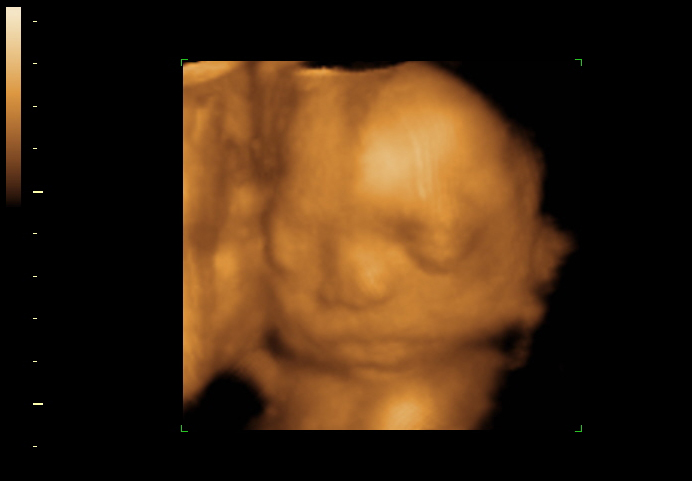

4D Fetal Imaging

HD, 4D and 3D ultrasound in Loving Arms Birth and Wellness Center in Ocala Florida.